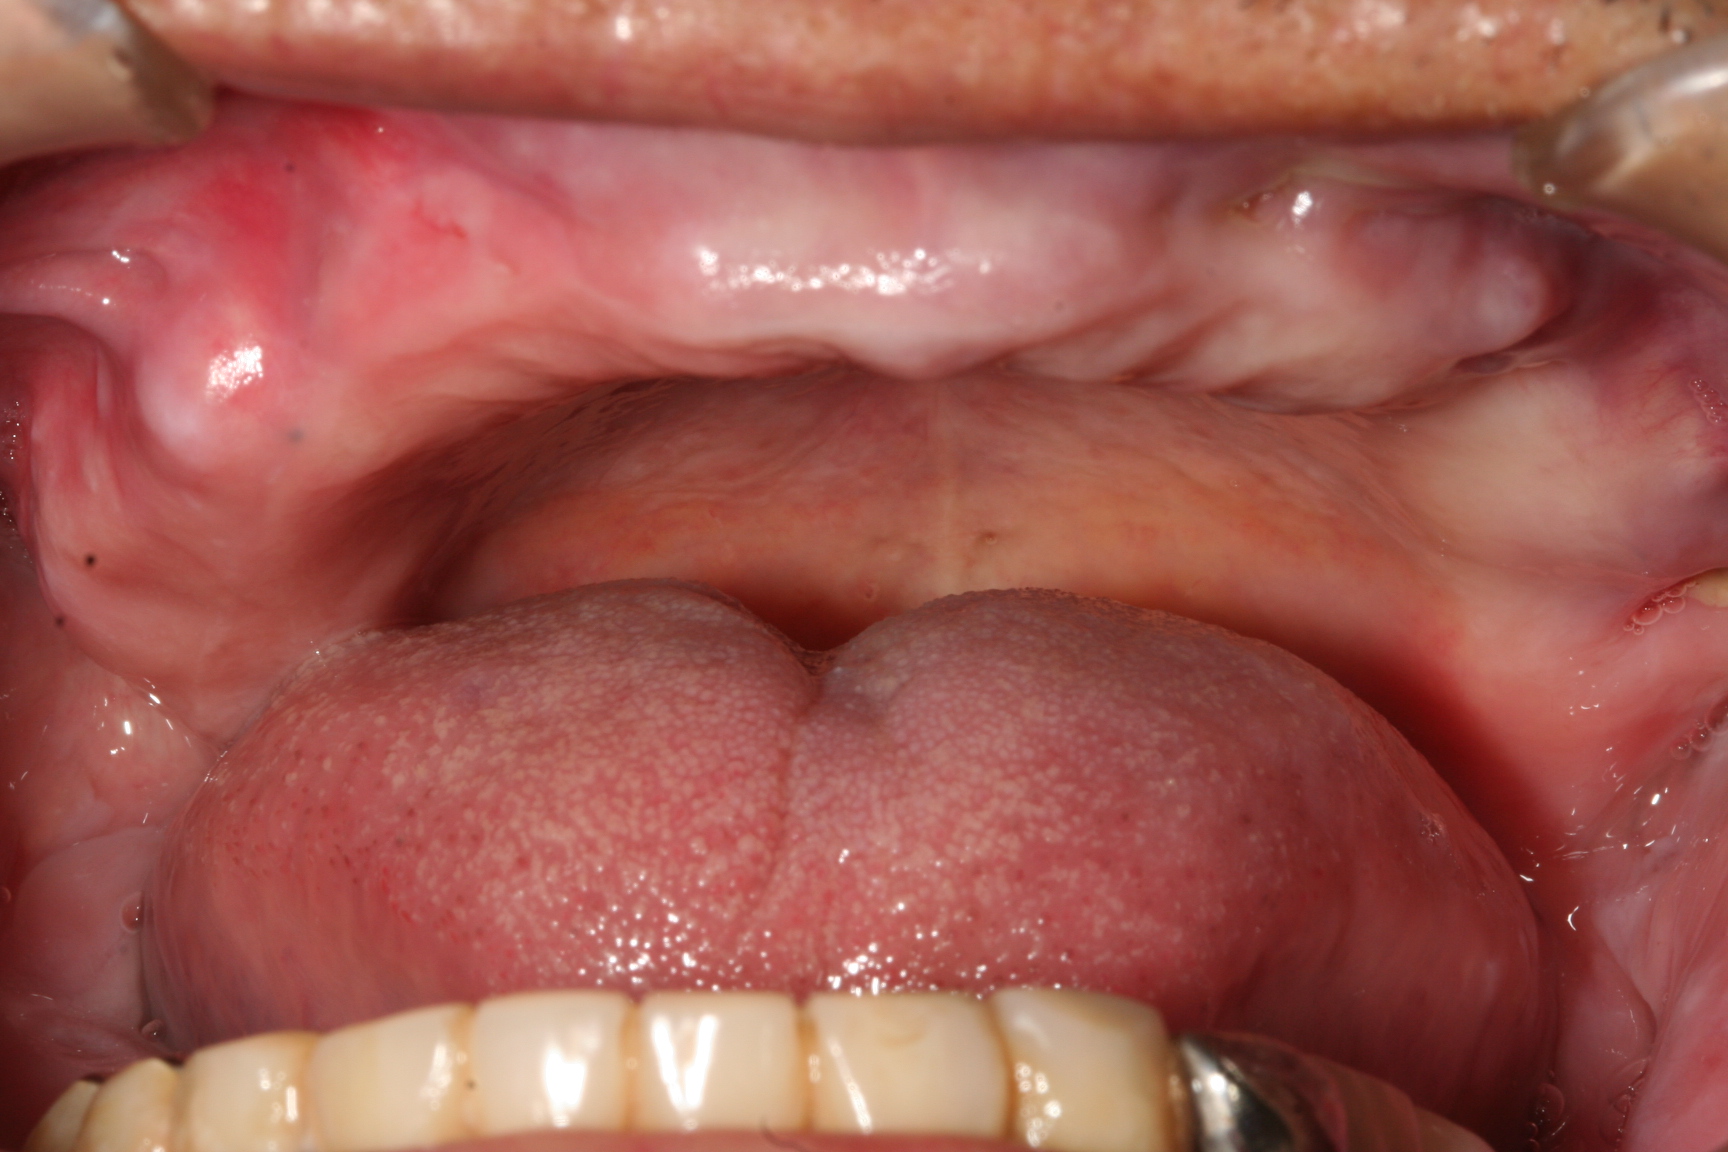

いきなり変なタイトルだと思われますが、全く関係無いわけではありません。ある歯科医療機関の調べでは、歯ブラシに100万個以上の細菌が発見されたというデータがあります。これはバケツ9杯分の汚水に匹敵する数で、便器bの水に含まれる細菌数の80倍にものぼるレベルでもあります。 これは風呂場や洗面所などの湿度が高い場所で歯ブラシを保管した場合の話ではありますが、それくらい口の中の細菌というのは繁殖率が高いのです。 歯ブラシを置く場合はなるべく乾燥し易い場所で保管しましょう。 逆に考えると歯磨きをしない口の中というのはどういう状態になるのか大体想像がつきますね。 その繁殖した細菌を飲み込んだらどうなるでしょう。胃潰瘍、胃ガン、心筋梗塞 等々沢山の病気を引き起こします。

歯医者の世界では、お尻の〇〇より口の中が”汚い”(細菌レベルで)というのが一般的に言われています。 汚い話で申し訳ありませんが、本当のことです。